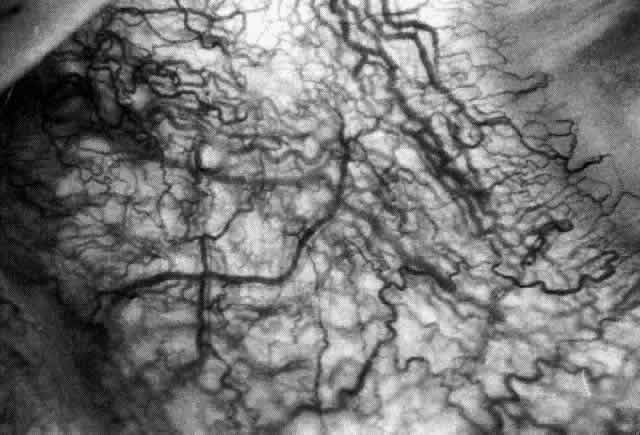

ARTERIAL PHASE Anterior Episcleral Arterial Circle The anterior ciliary arteries run radially toward the limbus within Tenon's capsule, giving few, if any, branches until they reach the anterior part of the globe. Their positions are very variable, and they do not always follow the rectus muscles. They bifurcate 2 to 5 mm behind the limbus, and each division runs forward and circumferentially to anastomose with a branch from an adjacent artery. This results in an anterior episcleral arterial circle (Figs. 3 through 5). The divisions of the anterior ciliary arteries are typically superficial at their origins but run deeper at their anastomoses. They occasionally dip too deep to be seen in fluorescein angiograms (Fig. 6).

From the anterior episcleral arterial circle, four distinct circulations are supplied: episcleral, anterior conjunctival, limbal, and iris. Episcleral Circulation Immediately after their origin by bifurcation of the anterior ciliary arteries, the contributions to the anterior episcleral circle divide again to give recurrent branches that run posteriorly and subdivide to form a netlike episcleral plexus (see Fig. 5; Fig.7). The variability of the positioning of the anterior ciliary arteries inevitably leaves large areas of episclera far from such an arterial supply (see Figs. 4, 6, and 7). These areas receive other posterior branches from the episcleral circle. Where the circle runs deep within the sclera, such branches appear as isolated perforating vessels (see Fig. 6). They fill very shortly after the episcleral circle, and they also divide repeatedly as they run posteriorly.

Anterior Conjunctival Circulation Throughout their superficial course, the arteries of the episcleral circle give off fine loops that run forward into the limbal reflection of the conjunctiva before curving back radially and dividing to form the lacework of the anterior conjunctival capillary plexus (see Fig. 2). The delicate column of blood within the anterior conjunctival loops may be punctuated by a string of individual erythrocytes, suggesting that the lumen is approximately 12 μm in diameter. Anterior conjunctival loops may also arise from perforating posterior branches of the episcleral circle (see Fig. 6). The anterior conjunctival circulation, supplied by the anterior ciliary arteries, always fills before the posterior conjunctival circulation, which is derived from the posterior tarsal vessels (see Figs. 4 and 5). The watershed zone between these sources can fill very late (see Fig. 5). However, anterior conjunctival loops do sometimes anastomose with arteries of similar caliber derived from the posterior tarsal circulation. Limbal Arcades Limbal arcades are supplied by anterior branches from the episcleral circle. Their origins are often shared with those of the anterior conjunctival loops, and, where the circle runs deep, they too are derived from the perforating posterior branches. They often fill very late during a normal angiogram (see Fig. 7). The limbal capillary loops never leak fluorescein, even during high-dose angiograms, suggesting that their endothelial cells are united by tight junctions. Iris Vessels The first flush of fluorescein within the anterior episcleral arterial circle always coincides with filling of the radial arterioles of the iris. It may be implied from this that the iris receives a major supply from the anterior ciliary circulation (see Fig. 6). In some angiograms, the iris circulation appears to derive directly from the episcleral circle. This raises the possibility that the “major circle of the iris” and the episcleral arterial circle are less distinct entities than has hitherto been presumed. VENOUS PHASE Anterior ciliary veins accompany the arteries, but there is no well-organized venous ring corresponding to the anterior episcleral arterial circle. The posterior episcleral branches of the arterial circle are paralleled by centripetal venules, and looping anterior conjunctival venules are interspersed between the arterioles (see Figs. 4 and 5). The posterior conjunctiva drains back into the tarsal circulation. CAPILLARY PHASE The episcleral capillary net is often difficult to discern below the more prominent conjunctival circulation. It is most clearly seen when the conjunctival circulation fills late for anatomic or pathologic reasons. The anterior conjunctival capillary plexus forms an interlacing network between the anterior conjunctival arterioles. Perfusion of the watershed zone that separates the territories supplied by the anterior ciliary and posterior tarsal systems may be delayed by as much as 15 seconds after first flush (see Figs. 5 and 7). However, this region is often crossed by arteriolar anastomoses between the two circulations, and the destination of venous blood is irrespective of its origin from the anterior ciliary or posterior tarsal circulations. |